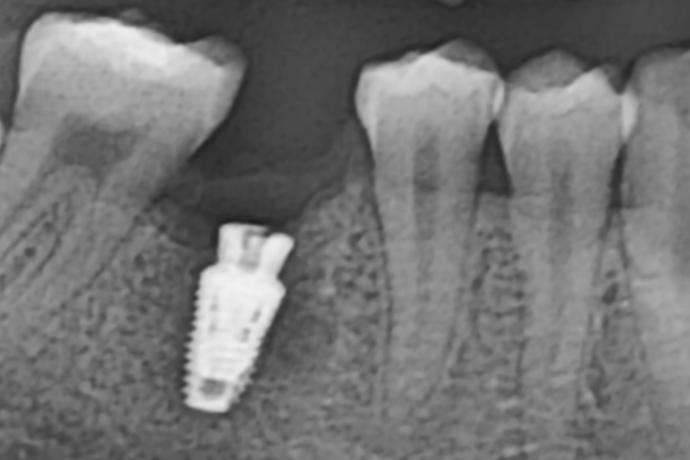

術中-

拔除殘根並立即植入人工牙根